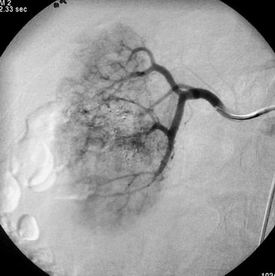

Obrázek 1 - angiografie pravé ledviny před léčbou s výraznou maligní vakularizací

V první fázi výkonu provádíme přehlednou diagnostickou angiografii abdominální aorty a selektivní nástřik renální tepny k posouzení cévního zásobení postižené ledviny (časté jsou varianty v počtu zásobujících tepen).